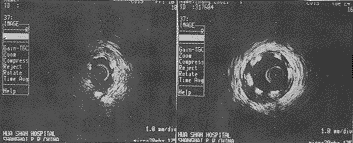

全部患者在支架植入前后均顺利完成了靶病变处的IVUS检查。其中1例支架植入前在超声探头经过靶病变时出现一过性血管痉挛并有心绞痛发作,冠脉内给100μg硝酸甘油后迅速缓解。在靶病变处,钙化斑块3例,混合斑块4例,纤维斑块4例,软斑块4例。偏心斑块11例,同心斑块4例。15例在PTCA后IVUS发现13例存在夹层,其中一些伴有管腔内的小内膜片(pocket flaps)(图1)。造影发现7例存在夹层(均被IVUS证实);而造影未发现的夹层,IVUS却发现了6例。15例支架经10~14atms扩张10~30秒植入后,虽冠脉造影显示结果满意,但IVUS却发现只有4例膨展贴壁良好(图2),另11例支架植入后存在游离腔,贴壁不佳,膨展不完全(图3)。15例中符合IVUS支架植入最佳标准者仅占27%(4/15),有3例(20%)在支架边缘处发现内膜撕裂或小裂隙。支架植入前后IVUS参数变化见表1。

图1 IVUS示PTCA后斑块破裂、内膜撕裂(A),并可见管腔内有小内膜片飘动(B)